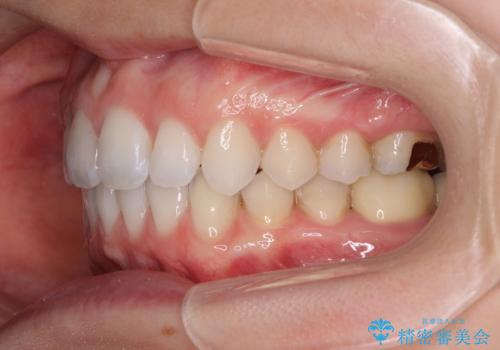

深い咬み合わせと奥歯のむし歯 総合歯科治療

- 奥歯の虫歯と前歯のデコボコや突出感を気にして来院された患者様です。

上顎歯列が、下顎に対して前方にありましたが、口元に出っ歯の印象がなかったため、親知らずを抜歯した上で、上顎歯列全体を後方に移動させることとしました。

咬合力が強いため、アンカースクリューを使用し、ワイヤー装置にて矯正治療を行うこととしました。

矯正治療後は、奥歯の虫歯や銀歯を補綴・修復治療することとしました。

上顎歯列を下顎に対して4mmほど移動させる必要があったため、治療は長期化することが予想されましたが、患者様にはこちらの期待以上にゴムかけなどに協力いただき、補綴治療も含めて2年強で終えることができました。